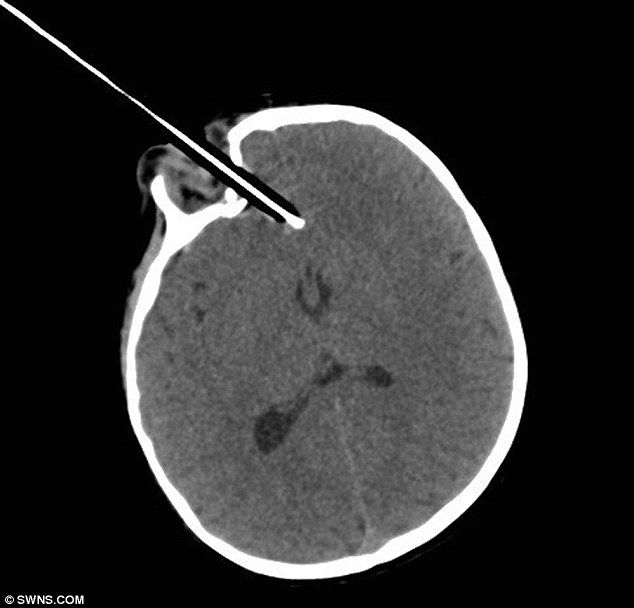

Двухлетняя девочка Рен Бовелл несла в руках карандаш и случайно упала с лестницы возле дома. Карандаш заострённой частью вонзился ей в глаз, девочку сразу доставили в больницу где четыре часа врачи боролись за её жизнь удаляя карандаш из черепа.

По словам врача девочке очень повезло,карандаш остановился в миллиметре от мозга и нечего не задел. Сейчас жизни девочке ничего не угрожает.